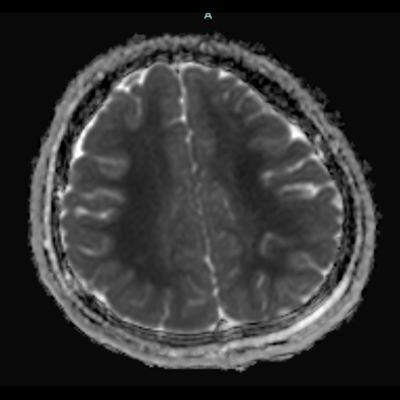

66 yaş, E

Kardiak arrest, 10 dk CPR öyküsü